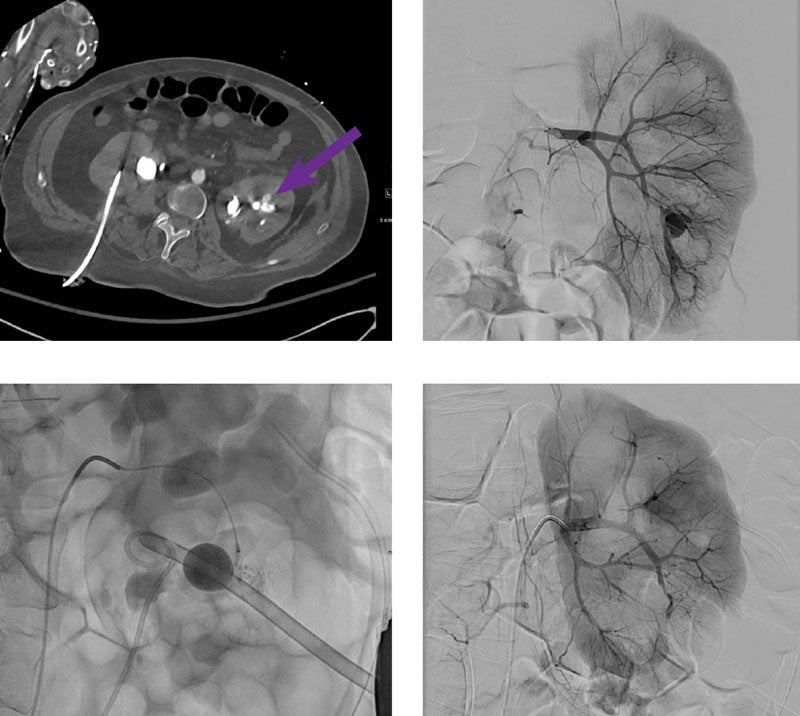

Post-PCNL renal bleed embolization

Courtesy of Dr. Rahul Patel I Mt. Sinai Hospital, NY

35-year-old male with recurrent multidrug resistant pyelonephritis/UTI in the setting of bilateral staghorn calculi and a left ureteral stone, presented with large volume hemorrhage after removal of percutaneous renal access post left nephrostolithotomy, with temporary balloon tamponade of the hemorrhagic tract via placement of a 20 Fr Foley catheter within the tract.

Post-PCNL CT angiogram demonstrates an 11 mm left renal lower pole pseudoaneurysm immediately adjacent to the 20 Fr Foley catheter within the nephrostomy tract.

5 Fr left common femoral artery access was obtained. An angled guide catheter was advanced into the left main renal artery and angiography was performed demonstrating a left renal lower pole pseudoaneurysm. A 2.8 Fr Progreat Microcatheter was advanced into a 5th order anterior lower pole left renal artery branch with its catheter tip positioned immediately proximal to the pseudoaneurysm. 0.2 mL of Obsidio Embolic was injected into the pseudoaneurysm and feeding branch until the feeding branch was filled. The Foley cath was left in the tract with the balloon deflated for the duration of the procedure.

Post-intervention angiography from the left main renal artery demonstrates complete stasis in the anterior lower pole feeding branch and no residual filling of the pseudoaneurysm, with preservation of at least 90% of the left renal parenchyma. Two weeks post-procedure, a left ureteral stent was placed, and the left percutaneous nephrostomy Foley catheter was removed without evidence of additional bleeding.

Scan images from Obsidio case.